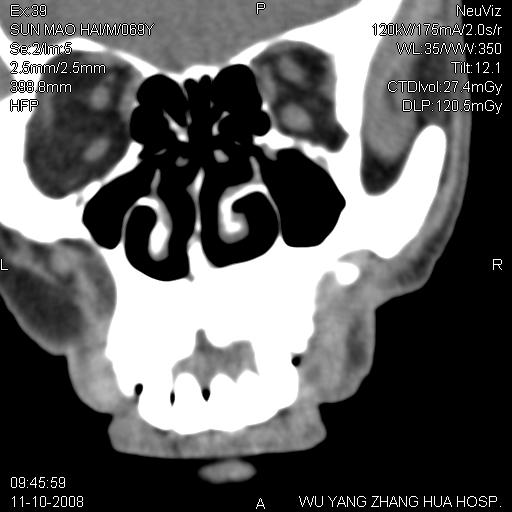

标题: CT16568:右面部瘘管半年余,无其它不适. [打印本页]

标题: CT16568:右面部瘘管半年余,无其它不适.

考虑右上颌异位齿(或斜向阻生齿)并根尖脓肿。

右上颌异位齿(或斜向阻生齿)

1.右上颌异位齿

2.右上颌化脓性骨髓炎

3.右下鼻甲肥大

支持三楼意见。(这种长法还真少见,再长再尖点就成獠牙了。)